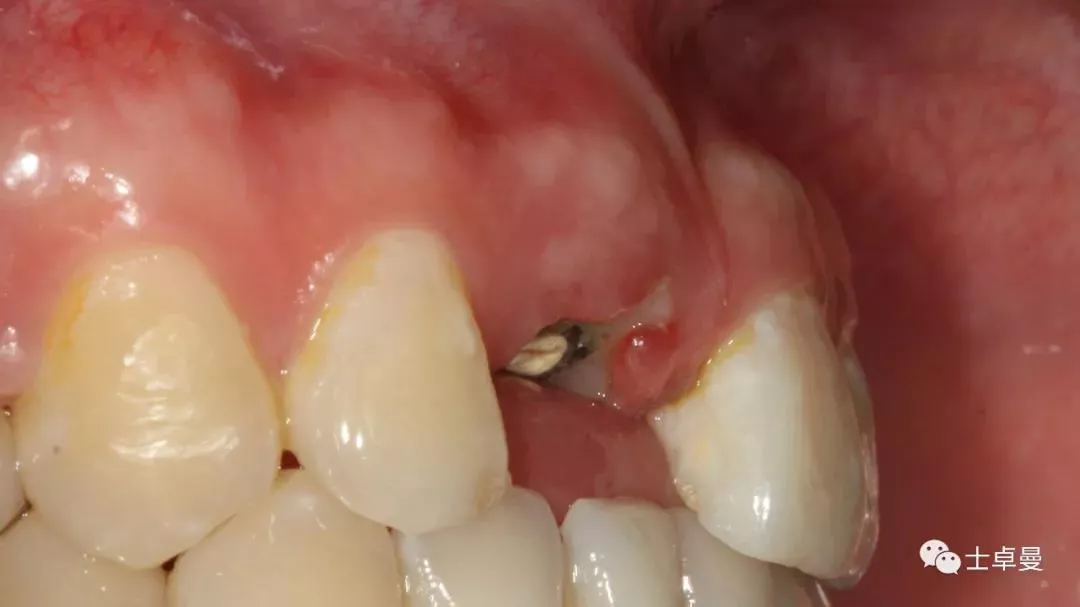

种植体植入后,植体唇侧间隙内填塞骨粉0.25g,胶原骨100mg,安放愈合帽,明胶海绵暂时封闭创面

术后即刻CT示,种植体植入位置理想

术后即刻制作个性化愈合帽

上部制作马里兰桥临时修复体

术后10天复查,软组织无炎症

术后1个月,取下马里兰桥,可见骨弓轮廓可,软组织无炎症